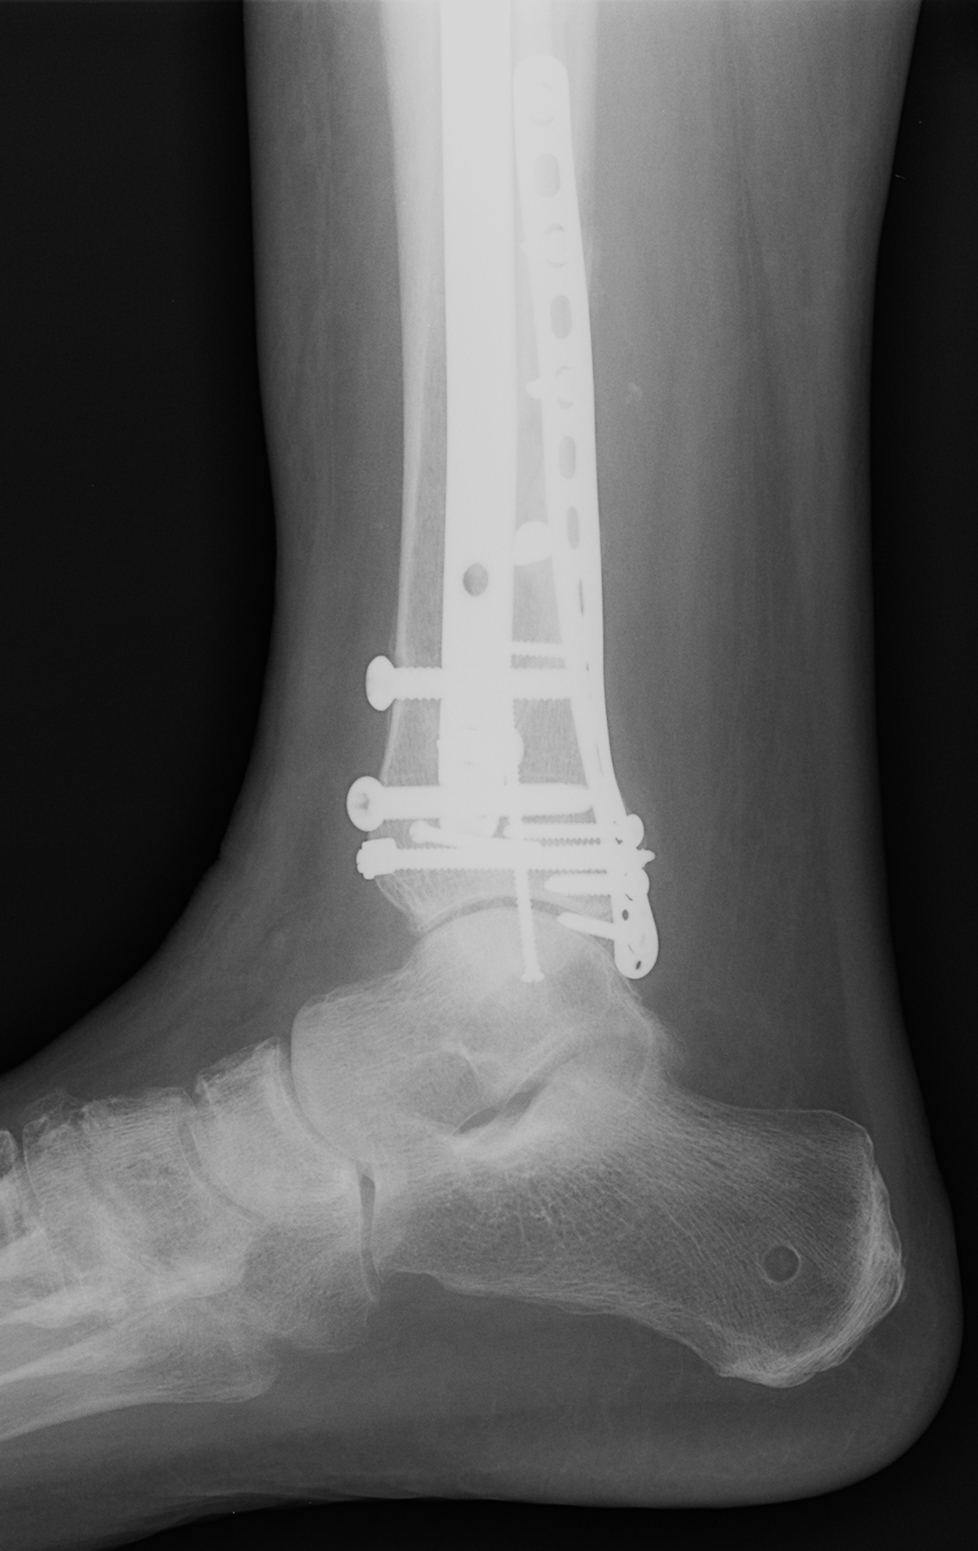

Fracture surface

Fracture surface 114 фото